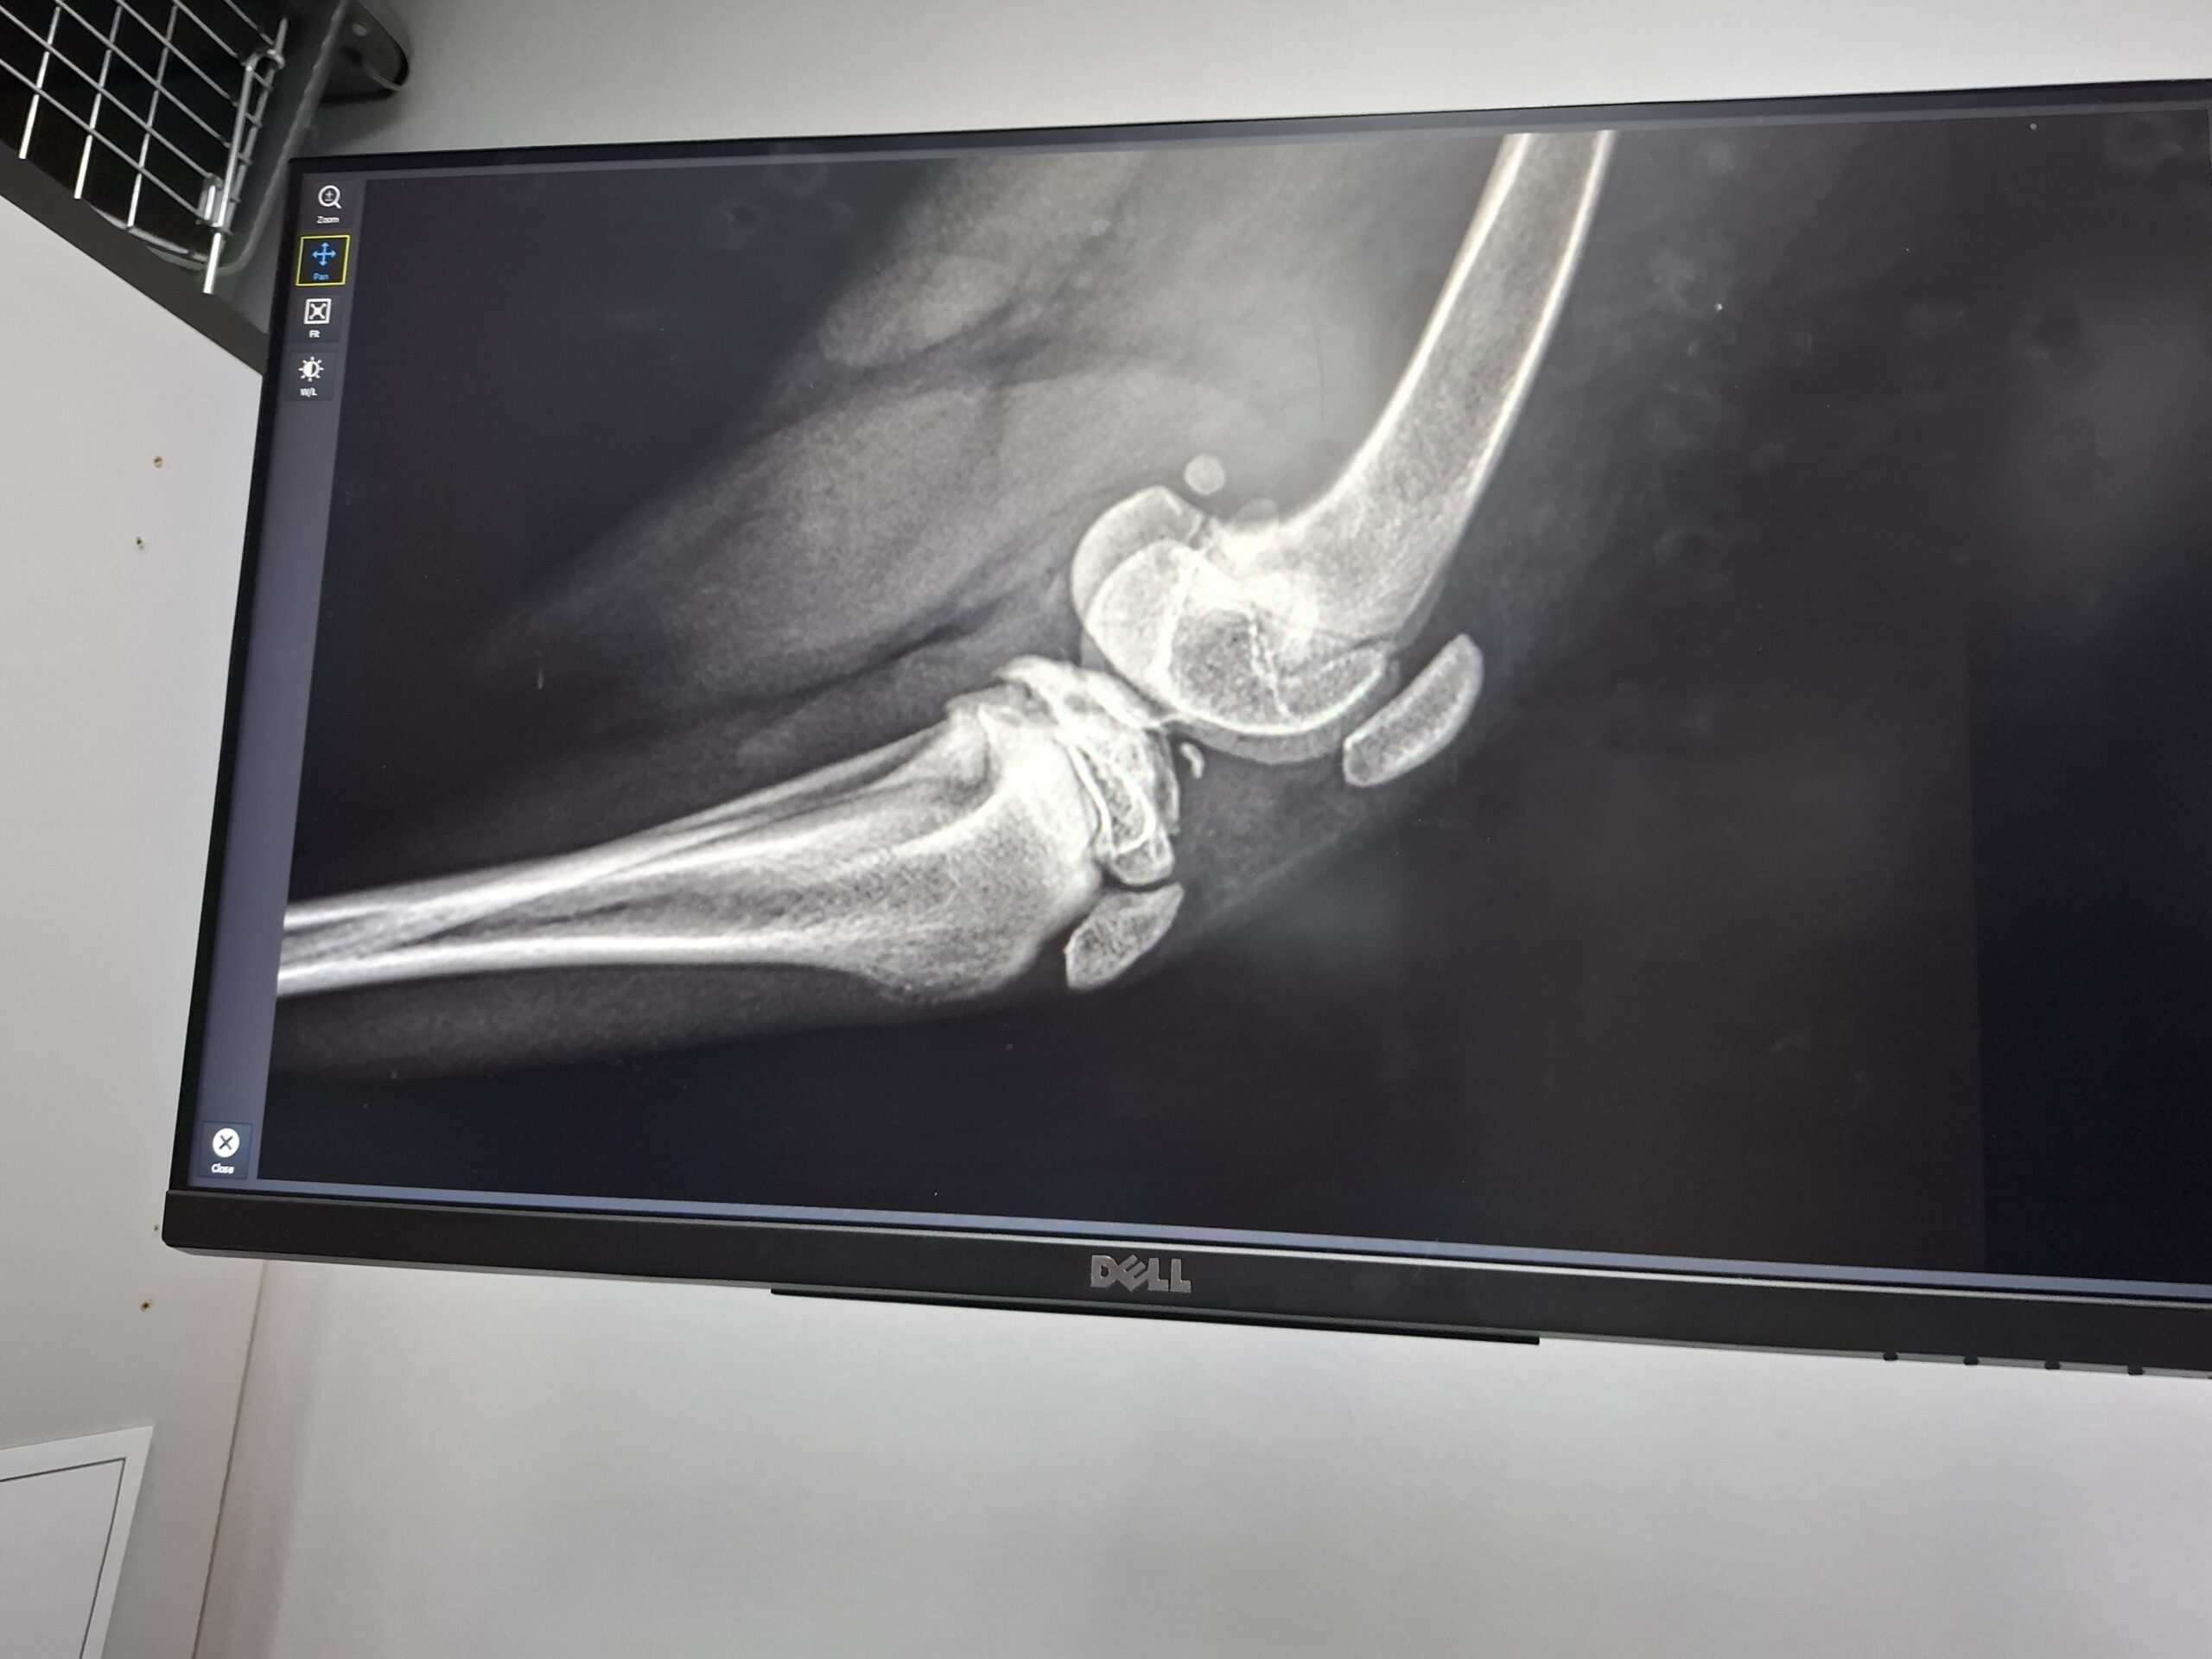

Los ging es nach Ploesti zum Tierarzt – einmal Röntgen. Dieser stellte fest, dass der eine Knorpel im Knie nicht fest sitzt. Nun muss Murphy ein anderes Futter haben, damit er nicht so schnell wächst und viel viel Bewegung. Anfang 2026 kann er dann operiert werden und ein ganz normaler Hundejunge ohne nachhaltige Probleme sein.

Leider benutzt er ein Hinterbein nicht richtig, sodass er in naher Zukunft geröngt werden muss.